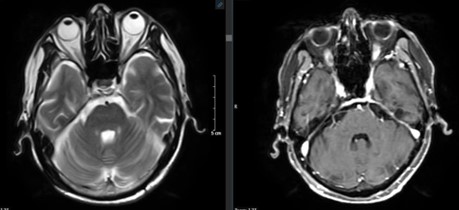

Hình ảnh chụp cộng hưởng từ sọ não sau 3 chu kỳ điều trị hóa chất:

Trước điều trị

Sau điều trị

Hình 4: Hình ảnh chụp cộng hưởng từ sọ não trước và sau điều trị

Nhận xét: Trước điều trị hóa chất xuất hiện hình ảnh nhu mô não có các nốt tổn thương nhu mô não hai bên ngấm thuốc mạnh sau tiêm, có phù não rộng xung quanh, tuy nhiên sau điều trị hóa chất 3 chu kỳ, không còn thấy hình ảnh tổn thương thứ phát tại não.